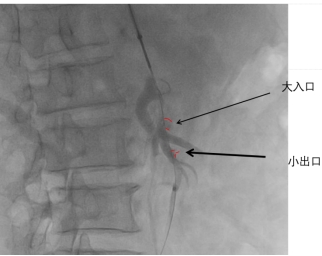

肠系膜上动脉夹层的手术风险高,可能出现术中血管破裂、术后肠道缺血等并发症,在与患者家属充分沟通后,首选腔内介入治疗。经过积极准备,在叶志东主任、樊雪强主任、郑夏医生、贺斌医生的共同努力下,对患者进行了肠系膜上动脉支架联合夹层动脉瘤栓塞治疗。支架释放成功,假腔显影明显减少,肠系膜动脉真腔供血改善,动脉瘤被“封堵”!

术中DSA造影